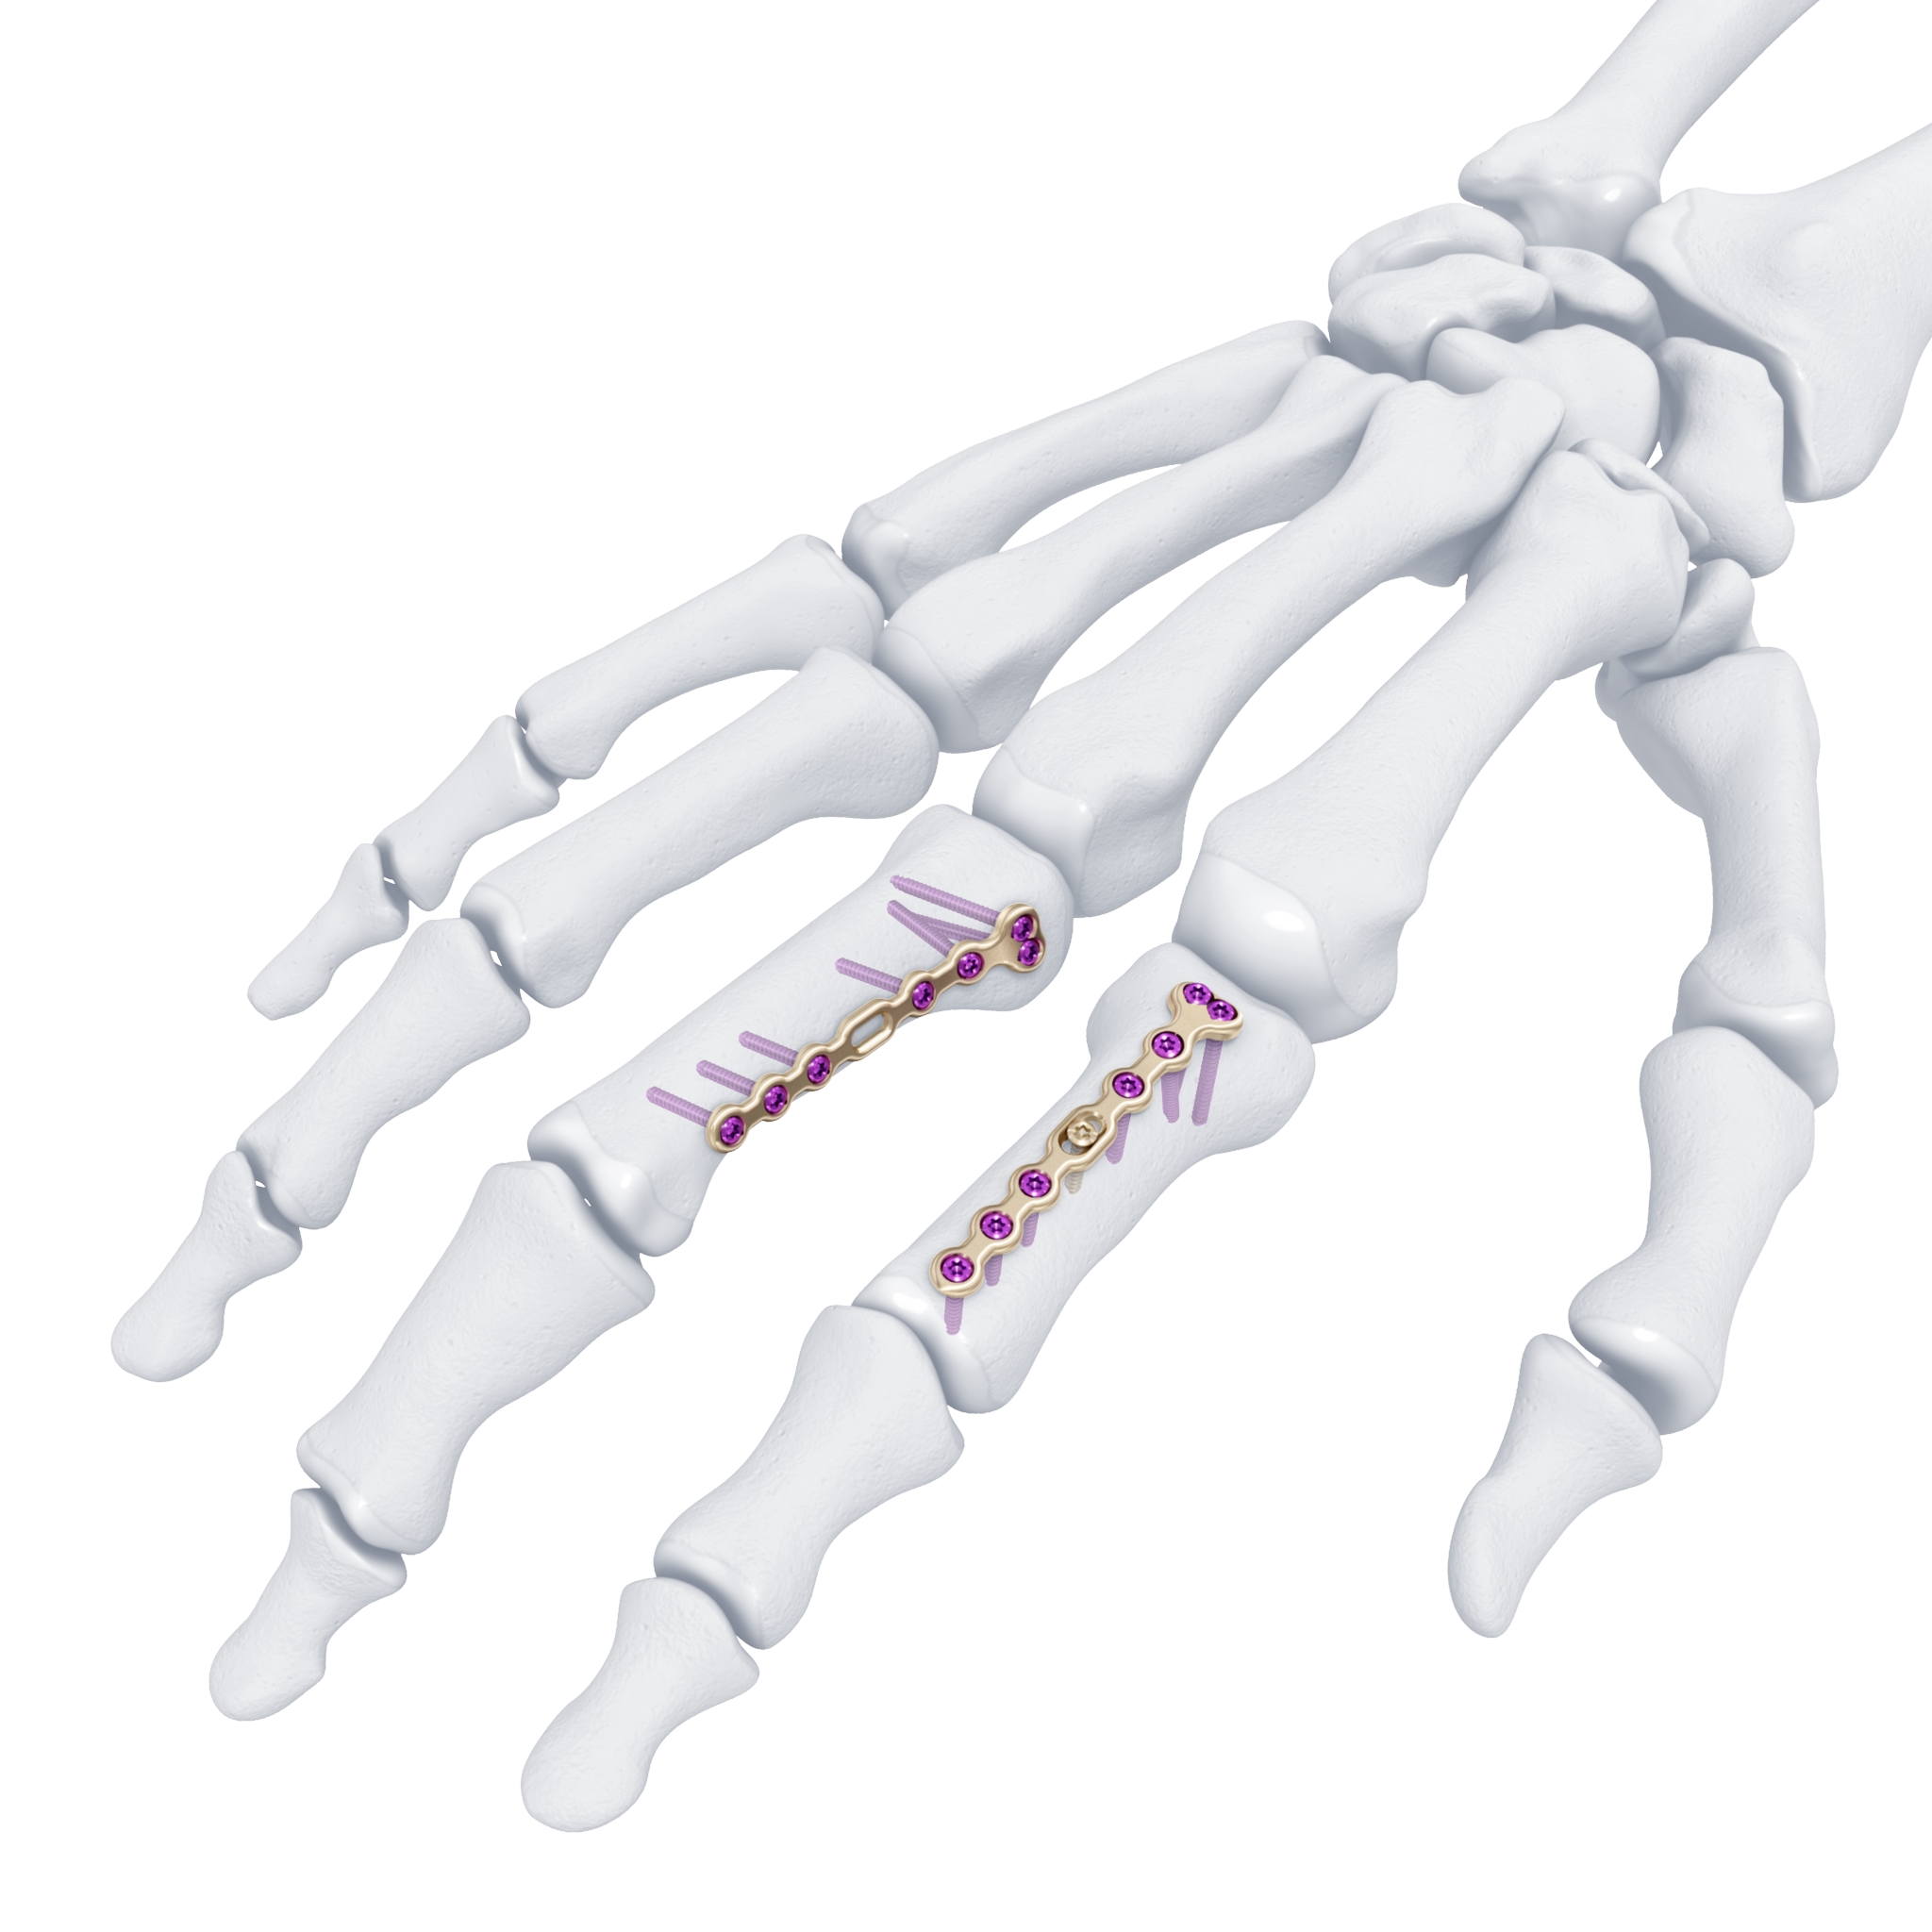

The previously approved Mini Fragment and Compact Hand System standard plates were designed to meet the needs of small bone fixation. The evolution of such internal fixation in the hand to now include variable angle technology (Fig 1) provides a perfect display of a variety of fixed angle devices that are more anatomically adapted with a lower profile design to accommodate the gliding structures of periarticular zones of the hand. The volume of implant beneath the extensor apparatus has been reduced both through plate design and the inclusion of smaller dimension implants (1.3 mm system).

The only fixed angle devices available in earlier systems were blade plate designs. In the new Variable Angle Locking Hand System, there exist a greater choice of implants which enable the application of axial stability and fixed-angle constructs in challenging fractures. Anatomically preformed plates also result in less bulk and a lower need for plate adaptation (Fig 2). A greater selection of fixed angle implants will allow for a wider range of application in osteopenic bone.

For reconstruction applications, a variety of implants that provide precise rotational adjustment have been added. Small rotational deformities of the digits are common and have a greater functional impact than other long bone deformities. These implants provide fine adjustment capabilities. Integration of variable angle locking technology (VA-LCP) into the 1.5 mm and 2.0 mm systems allow for improved placement of screws in metaphyseal bone. Safer and more accurate screw placement in periarticular and juxta-articular positions is realized with the VA-LCP (Fig 3).